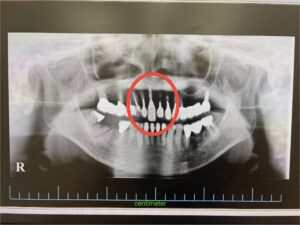

患者様は、前歯の神経を抜いた後にセラミックを被せていた歯が破折したため来院されました。

術前

今回は、歯を抜いた直後にインプラントを埋入する**「抜歯即時埋入」**という方法で治療を行いました。